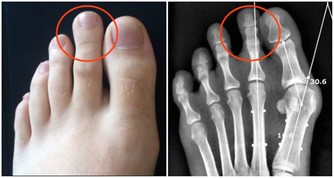

青光眼、痛風等特殊疾病患者需在醫生指導下喝水。